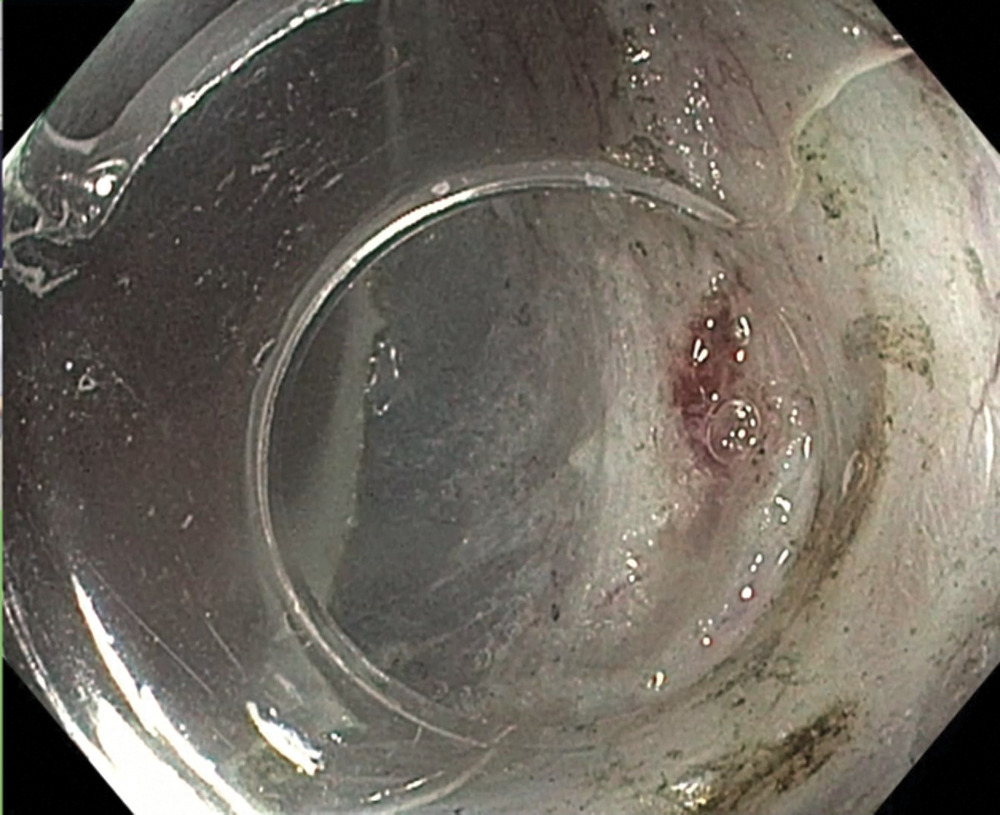

Следующий этап — лечебный. Была выполнена эндоскопическая резекция слизистой оболочки с опухолью с диссекцией в подслизистом слое ESD (рис. 8, 9,